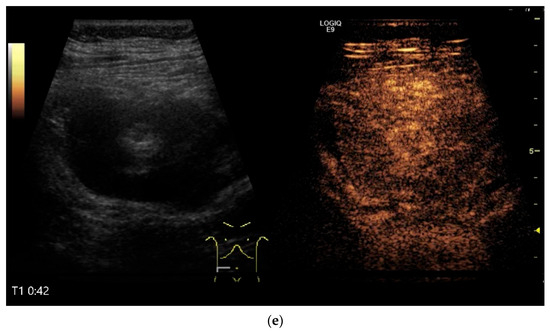

Figure 12.

GIST. Incidental finding of a 35 mm, slightly polycyclic, homogeneous hypoechoic mass in the left upper abdomen (a,b). This changes position with the movements of the small intestine. In CEUS with 1.2 mL SonoVue using the abdominal sector transducer (1–5 MHz), the mass shows homogeneous hyperenhancement in the arterial phase (c). The intensity then decreases (d). The tumor is marked with arrows in CEUS.